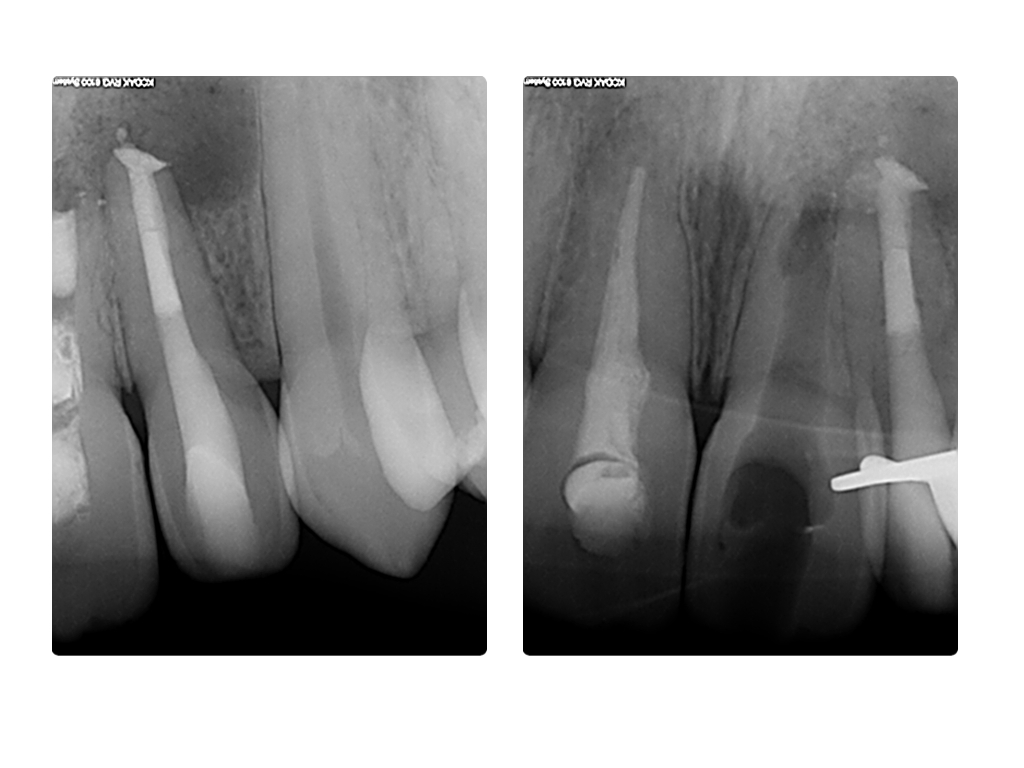

ws7.009 Veröffentlicht 27. Juni 2014 am 1024 × 768 in Einbahnstraße WSR (2) WF 22 WF und retrograde WF Entf, 21